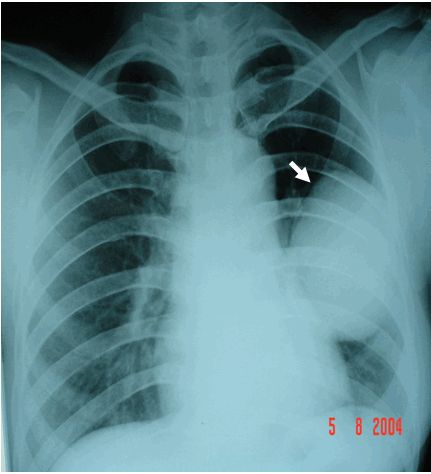

Khối u phổi: đám mờ trên phim Xquang phổi ranh giới không rõ

U phổi là một trong những bệnh lý có rất ít các triệu chúng lâm sàng rõ ràng. Đặc biệt là ở giai đoạn sớm của bệnh có thể không xuất hiện bất kỳ triệu chứng nào. Chụp CT Scan phổi độ phân giải cao có thể được chỉ định trên những bệnh nhân có các dấu hiệu lâm sàng của viêm phổi nhưng không thấy hình ảnh bất thường. Cùng eLip tìm hiểu những thông tin ngay dưới đây để hiểu rõ hơn nhé!